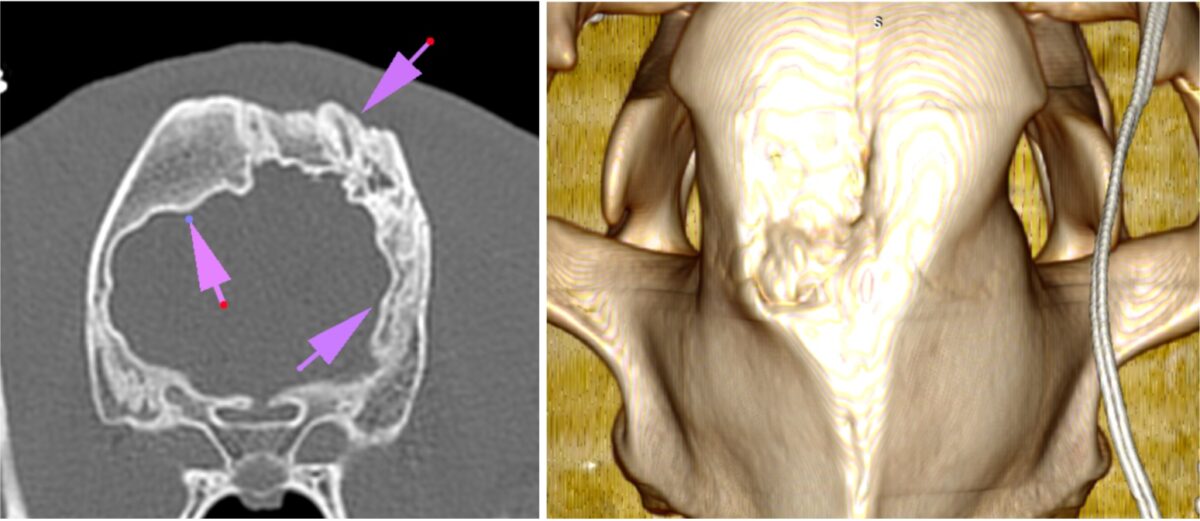

Uit de CT-scan werd duidelijk dat Tzigane een flinke afwijking aan zijn wervelkolom had, die mogelijk is aangeboren. Hierdoor is zijn borstkas misvormd en is er minder ruimte in de rechterkant van zijn borstholte. Hoewel Tzigane’s hart dus niet bijzonder groot bleek, was een er wel een deel van zijn longen aangetast. Dit komt waarschijnlijk door het gebrek aan ruimte in zijn borstkas.

Het meest opvallend was dat de koepel van zijn schedel (voorhoofds- en wandbeenderen) sterk verdikt was en naar de schedelholte groeide, waardoor er druk op zijn hersenen ontstond. Omdat Tzigane nog vrij jong is, lijkt hij hier nog geen last van te hebben. We zullen moeten afwachten hoe dit zich verder ontwikkelt.

Tzigane scan

De scan laat een duidelijke kromming van Tzigane's wervelkolom zien.

Ook is duidelijk letsel aan zijn schedel zichtbaar.